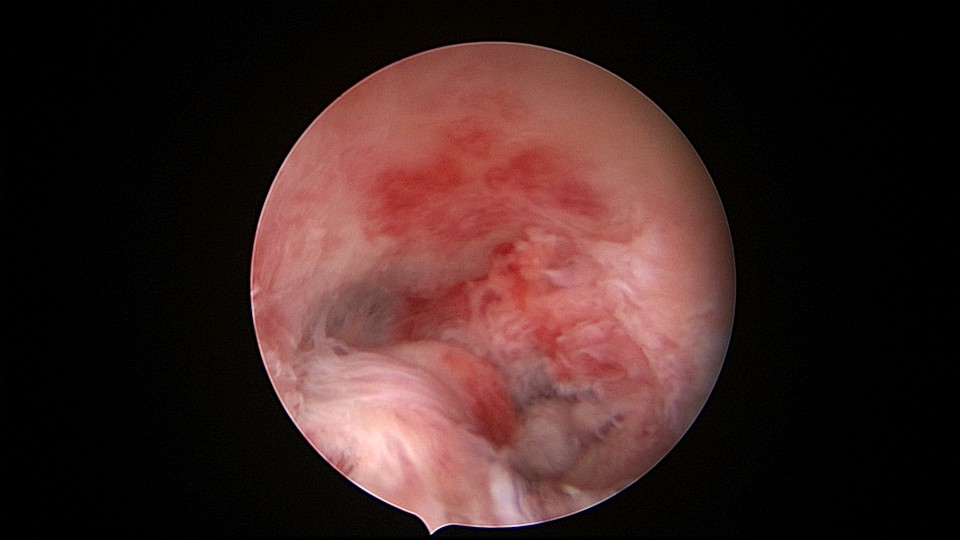

患者48岁,G5P1,剖宫产1次。安环20年,闭经3个月,外院取环失败,形成假道。子宫极度前倾前屈位,宫腔镜见宫颈管上段组织杂乱,左后壁假道,宫腔镜寻找到宫颈内口,艰难进入宫腔,爱母环位置正常,异物钳顺利取出,宫腔无其他异常。